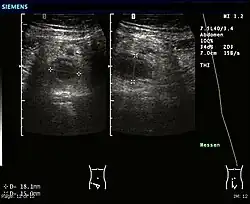

Abdominal ultrasonography, preferably with doppler sonography, is useful to detect appendicitis, especially in children. Ultrasound can show the free fluid collection in the right iliac fossa, along with a visible appendix with increased blood flow when using color Doppler, and noncompressibility of the appendix, as it is essentially a walled-off abscess. Other secondary sonographic signs of acute appendicitis include the presence of echogenic mesenteric fat surrounding the appendix and the acoustic shadowing of an appendicolith.[59] In some cases (approximately 5%),[60] ultrasonography of the iliac fossa does not reveal any abnormalities despite the presence of appendicitis. This false-negative finding is especially true of early appendicitis before the appendix has become significantly distended. Also, false-negative findings are more common in adults where larger amounts of fat and bowel gas make visualizing the appendix technically difficult. Despite these limitations, sonographic imaging with experienced hands can often distinguish between appendicitis and other diseases with similar symptoms. Some of these conditions include inflammation of lymph nodes near the appendix or pain originating from other pelvic organs such as the ovaries or Fallopian tubes. Ultrasounds may be either done by the radiology department or by the emergency physician.[61]

- Ultrasound showing appendicitis and an appendicolith.[62]

- Ultrasound of a normal appendix for comparison.

- A normal appendix without and with compression. Absence of compressibility indicates appendicitis.[59]